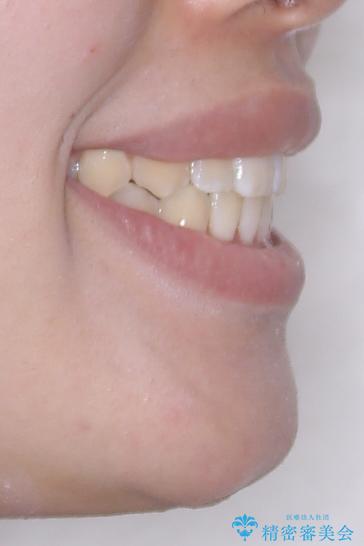

- 今回は「下の前歯のデコボコを治したい」と来院された患者様の症例をご紹介します。

患者様は「目立たない装置で矯正したい」との希望があり、当院では透明なマウスピース型矯正装置(インビザライン)による治療を提案しました。

診察してみると、下の前歯が並ぶためのスペースが足りないことが、歯並びがデコボコしている原因でした。

この計画により、デコボコだった下の前歯はしっかりと並び、わずか1年で治療を終えることができました

見た目が気にならないマウスピース矯正だったこともあり、患者様にも大変ご満足いただけました。